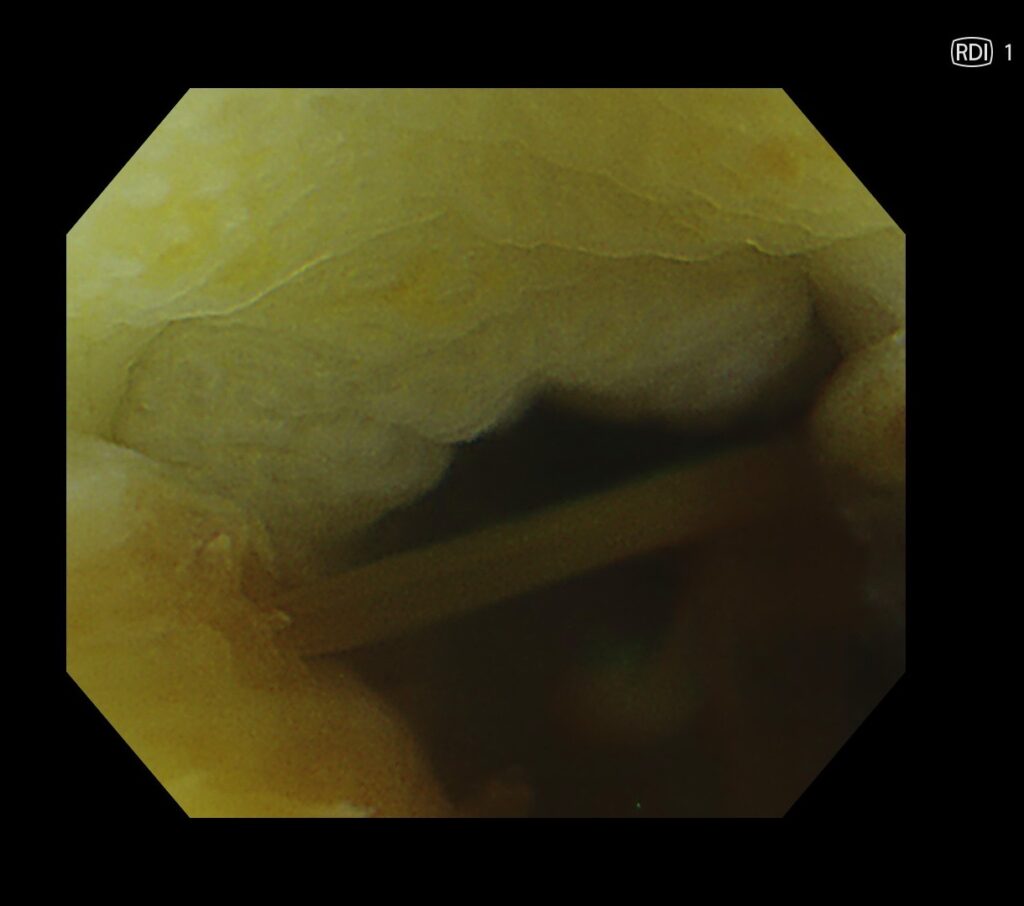

ここから、EVIS X1のRDIモード(出血源同定に役立つモード)の出番となります。

RDIにすると、脈をうちながら吹き出す動脈出血を視認できました。